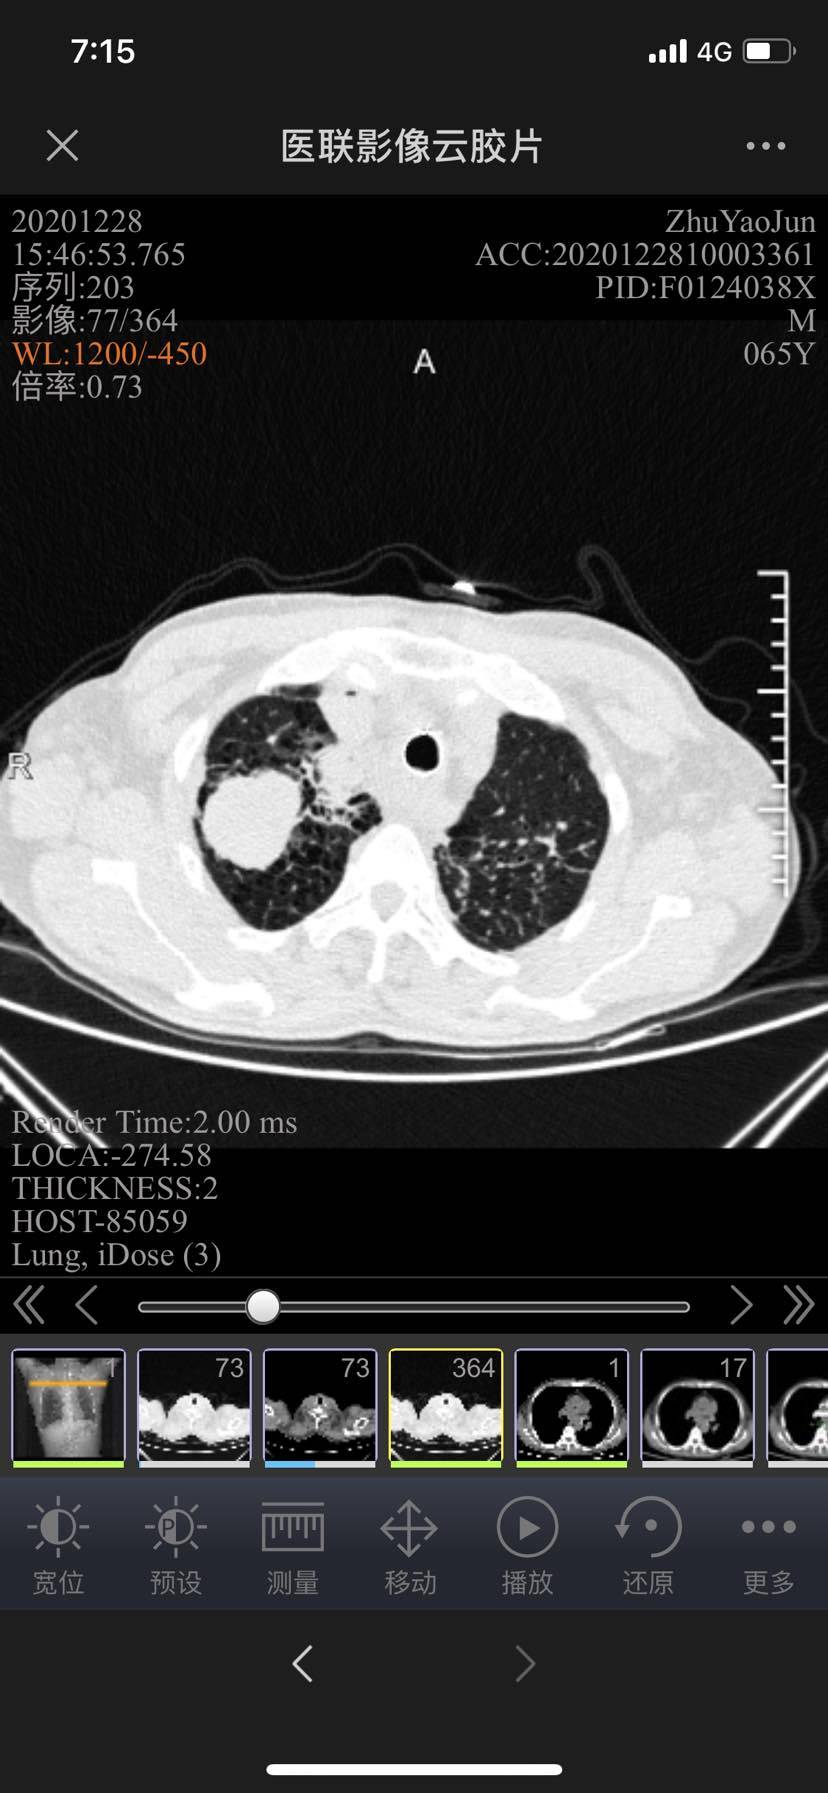

庆幸这次的年终考总算取得了一个阶段性的小胜利,ct显示纵隔内部分淋巴结缩小,自己认真对比了片子确实是肉眼可见的明显缩小了,最让我担惊受怕的气管压迫缓解不少!

12/28老片